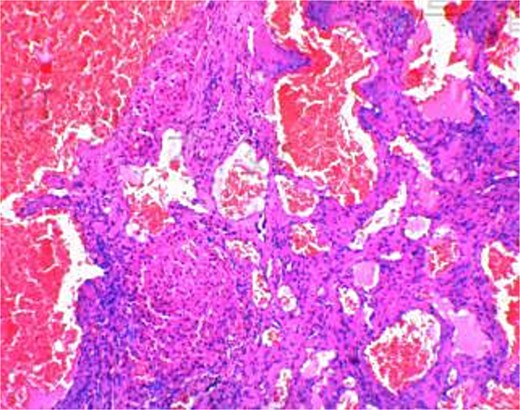

The 191-minute procedure incurred only 40 ml of blood loss and no postoperative complications. Postoperative pathology confirmed hepatic cavernous hemangioma (Fig. 3). The drainage tube was removed on postoperative Day 3, and the patient was discharged on Day 4.